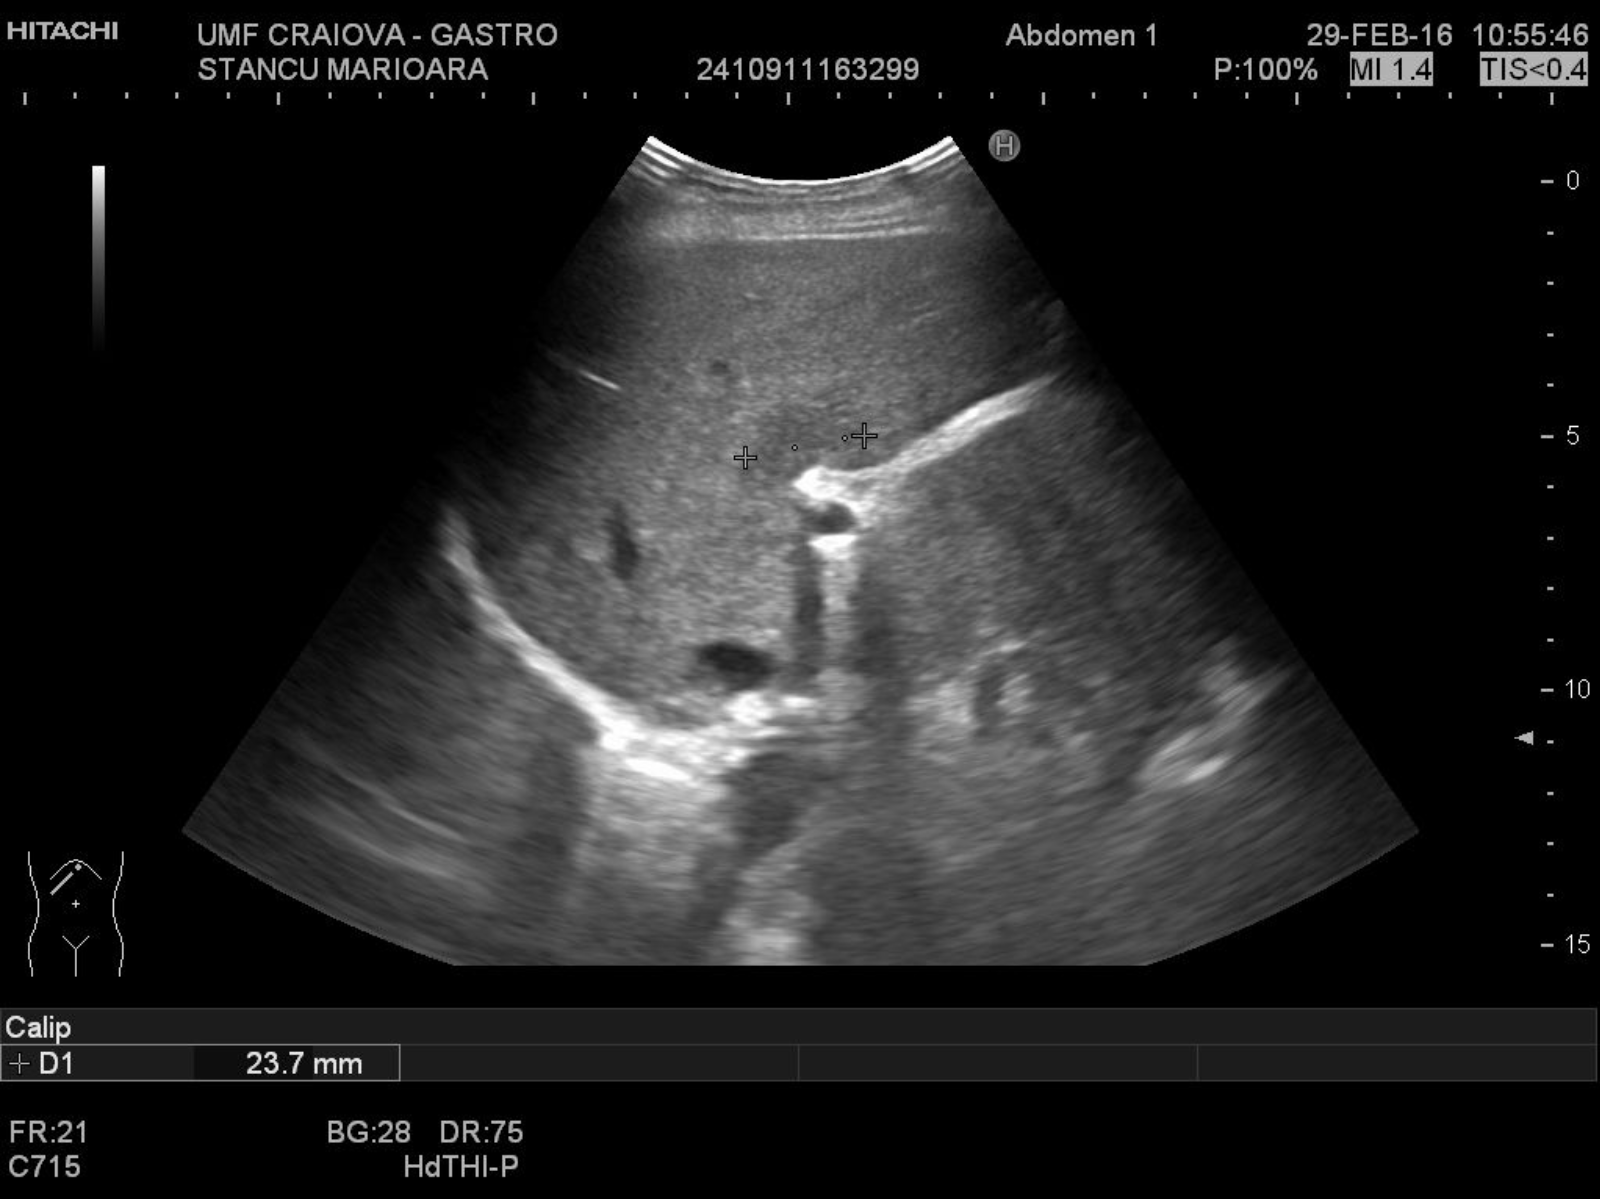

TITLE:  Focal fatty sparing of the liver

74 years old female –a hypoechoic mass anterior of the hepatic hilum

liver ultrasound, liver steatosis, focal fatty sparing